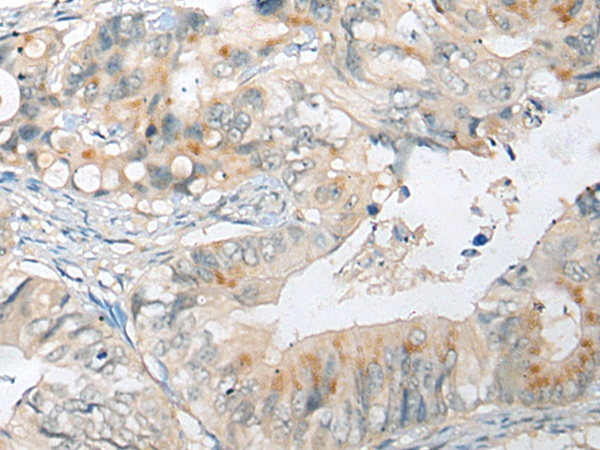

IHC (Immunohiostchemistry)

(The image on the left is immunohistochemistry of paraffin-embedded Human colorectal cancer tissue using 46469(CELSR1 Antibody) at dilution 1/30, on the right is treated with synthetic peptide. (Original magnification: x200))